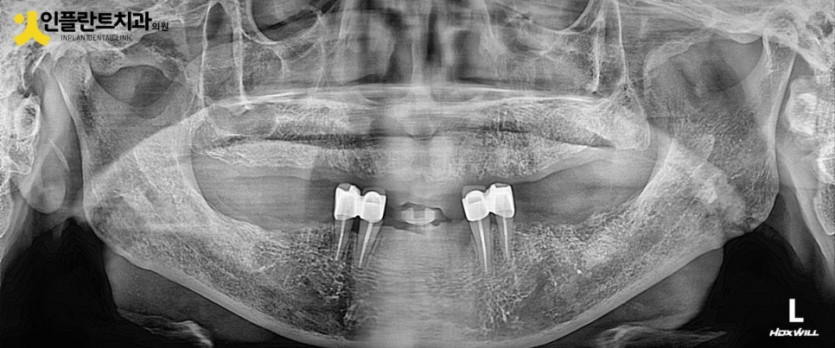

파노라마 사진을 보니 남아 있는 치아들 잇몸뼈가 전반적으로 많이 내려가 있어

많은 치아의 동요도와 그동안의 불편감을 예상할 수 있었습니다.

특히나 당뇨로 당조절이 잘 안되는 분들의 경우 치주질환이 더 악화되기가 쉬워서

그동안 관리가 어려우셨을 점들이 느껴졌습니다.